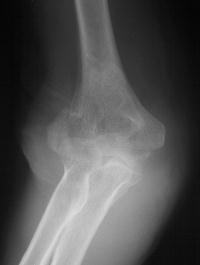

81 year old physically active woman sustained a left elbow fracture in a syncope related fall.

Lateral and central fracture component displacement.

Unusual contour visible at the medial metaphyseal flare.

This is seen on the lateral view to be the anterior half of the central articular surface.